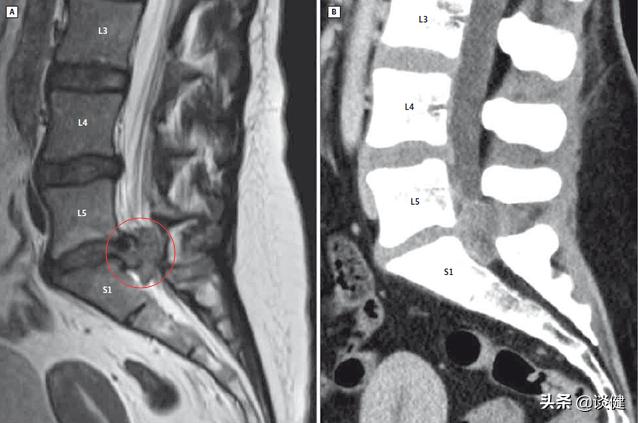

腰椎盘突出

●椎间盘突出症:我们的椎间盘,就是充当椎体与椎体之间的垫子,缓冲椎体的压力。其实它是比较软的。正因为如此,当我们的垫子受到挤压出现破裂或撕裂时,它就会向外突出。当它压在附近的神经上时,我们就会出现一系列的症状。就有这么一种情况,椎间盘突出恰好压在了下背部的坐骨神经上,它引起坐骨神经痛。